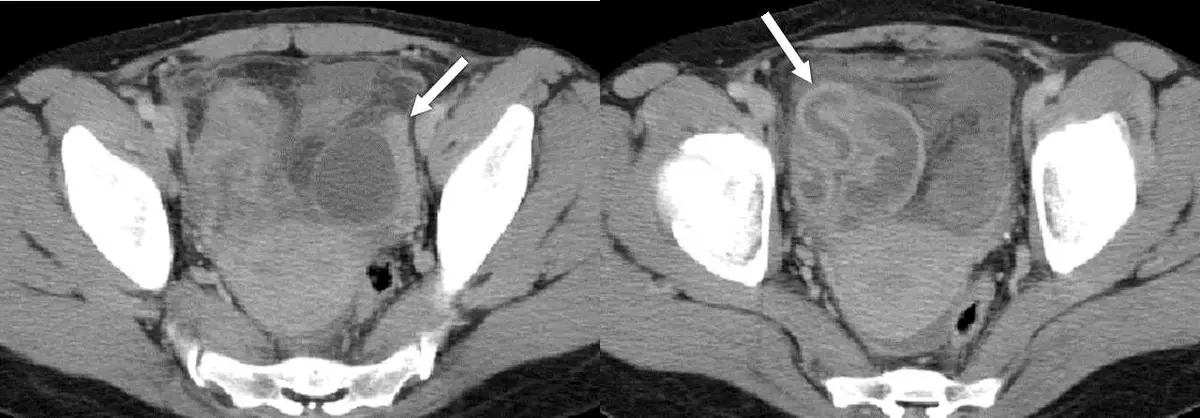

28 歲女性主訴發燒和下腹疼痛,電腦斷層檢查呈現如圖,箭號所指之敘述何者最正確?

輸卵管卵巢膿瘍(tubo-ovarian abscess, TOA)是骨盆腔炎(pelvic inflammatory disease, PID)的嚴重併發症,電腦斷層(CT)上呈現特徵性的附件區厚壁多房囊性腫塊伴周圍脂肪浸潤(fat stranding)與環形增強(rim enhancement),需與子宮內膜炎、子宮外孕及子宮頸癌鑑別。本題 28 歲女性有發燒與下腹疼痛,是典型 TOA 的臨床場景。

本題為骨盆腔電腦斷層(pelvic CT)橫切面,圖示並排的兩個連續切面,均有白色箭頭標示病灶。

右側(左圖,較低層面): 箭頭指向位於子宮右後方附件區的一個大型複雜性囊性腫塊,腫塊邊界欠清晰,囊壁明顯增厚且不規則,內部可見多房分隔(multilocular),囊液密度不均,周圍骨盆脂肪出現模糊浸潤(fat stranding),代表急性發炎反應向鄰近組織蔓延。子宮體(高密度圓形結構)位於中線偏左,與右側腫塊之間尚有間隙。

左側(右圖,較高層面): 箭頭指向相同病灶的上極切面,可見腫塊的另一個囊性腔室,形態迂曲,部分呈管狀延伸,符合擴張的輸卵管(pyosalpinx/hydrosalpinx)腔室形態,整體形成典型的「腸樣(sausage-like)」或「管-卵巢複合體」外觀。兩側膀胱(高密度充盈)及腸管